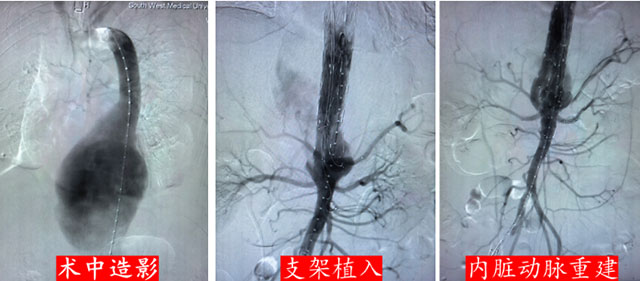

传统开放手术需要开胸或开腹,创伤大、出血多、手术时间长,对于瘤体已经破裂的王先生而言,是难以耐受的。此时,血管腔内治疗成为了首选,通过大腿根部的小切口,将覆膜支架经外周动脉送入主动脉,精准释放后,支架将破裂的动脉瘤与正常血流隔离开来,相当于在血管内部重新铺设了一条“新管道”,从而阻止血液继续外漏。

明确治疗方案后,介入·血管科团队在全麻下为王先生实施了主动脉腔内隔绝术,并同步完成腹腔干动脉、肠系膜上动脉及双肾动脉支架植入血管重建术。

团队历时8小时,成功隔绝动脉瘤,重建内脏动脉血供。术后,王先生转入CCU接受严密监护与精细护理。在多学科团队的持续协作下,生命体征逐步稳定,感染得到有效控制,脏器功能恢复良好,顺利出院。

当动脉瘤累及内脏动脉时,还可采用“开窗支架”“分支支架”或“支架植入重建”等技术,在封堵瘤体的同时,保留或重建重要脏器的供血,一次性解决“封堵破裂”与“重建血供”两大难题,为患者赢得了生的机会。